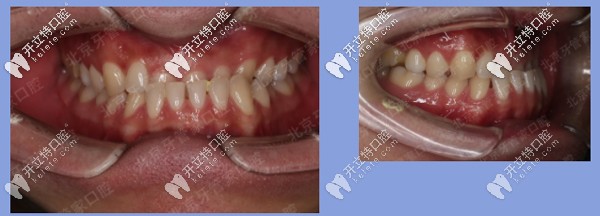

被矯治者基本信息:王先生,22歲,地包天,牙列散縫。

患者牙齒矯正前

前期檢查:反合(又稱地包天),骨性三類,磨牙關(guān)系三類。下前牙已經(jīng)發(fā)生舌傾,存在縫隙。

患者牙齒前期檢查

治療方案:內(nèi)收下牙列,上頜唇傾前牙,代償性掩飾治療。

矯治器:金屬固定矯正

患者地包天牙齒矯正中

矯正時長:23個月

矯正結(jié)果:上下前牙反合解除,上唇突度恢復(fù)豐滿,患者非常滿意。

患者地包天矯正后